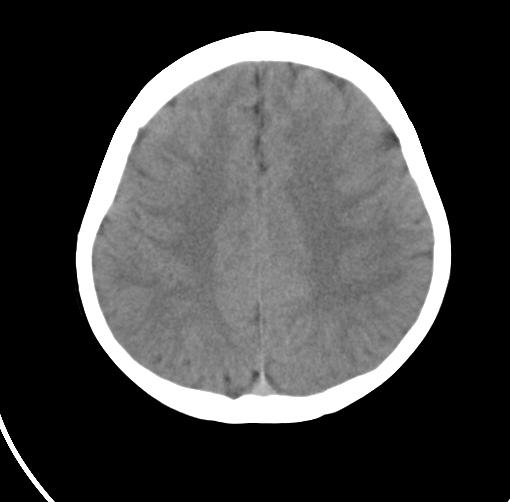

以下是引用sunjh2266在2007-7-31 23:35:00的发言:[br]脉络膜裂,是胚胎发育过程中脉络襞突入侧脑室下角构成脉络丛时形成,位于丘脑下部与海马之间,走行与海马平行。脉络裂内侧通于环池,外侧为侧脑室下角,前面是海马钩及杏仁体,后部与海马沟交通。脉络裂内有参与组成侧脑室脉络丛的脉络膜前动脉及脉络膜后外动脉及其分支走行。[br] mri轴位像,在大脑脚的前外侧多能显示脉络裂的前部,呈左右走行的含脑脊液间隙,前后内外分别与杏仁体、海马、海马钩及侧脑室下角相邻(图1);冠状位像,在扫及脑干的多个层面上,脉络裂均可被清晰显示,因而是显示脉络裂的最佳扫描方式。偏前的部分层面还可见到呈切迹状的海马沟走行于海马旁回内上方;矢状位像,海马旁回上方可见一分叉状裂隙,类似一斜卧的“入”字,接近水平走行的一撇为脉络裂,而由后上向前下走行的一捺为从扣带沟延续而来的海马沟。[br] [br]